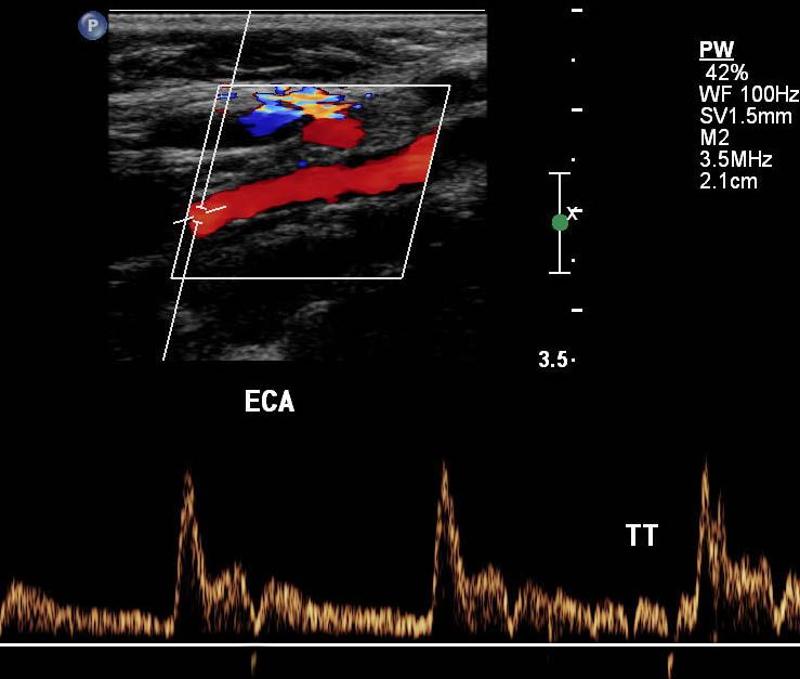

Explain the waveform of the ECA

high resistant

steep forward stroke

Forward flow during systole, low or reverse diastolic component

Where is the waveform?

ECA